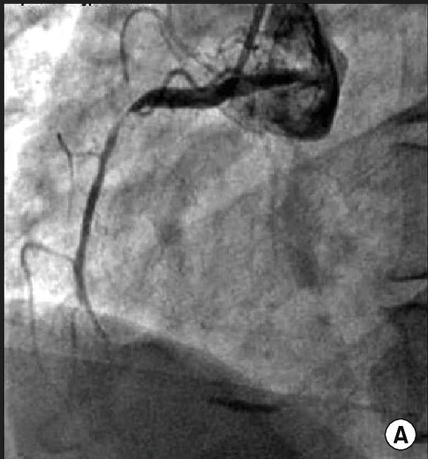

coronary angiogram

Diagnosis: Coronary spastic angina

Certainty: Certain

Author: Dr. Aqsa Ali

Date Published: Mar 12, 2026

Disease Specialty: Cardiology

Image Type:

2D